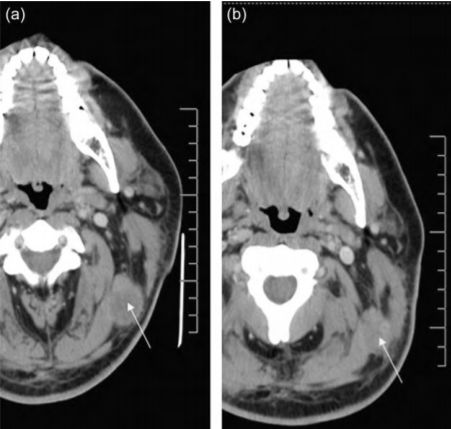

2008 年,美國拉什大學醫學中心的研究人員將外源擴增的 NK 異體細胞注入到黑色素瘤患者體內,結果發現,注入注入 NK 細胞后,該患者左上頸部腫瘤的體積明顯降低(從 3.15cm×2.54cm 減小至 2.46cm×1.76cm)。同時,該研究也為外源擴增的 NK 異體細胞是否可以大規模應用于治療黑色素瘤提供了一定的理論依據。

▲NK細胞治療前后對比圖